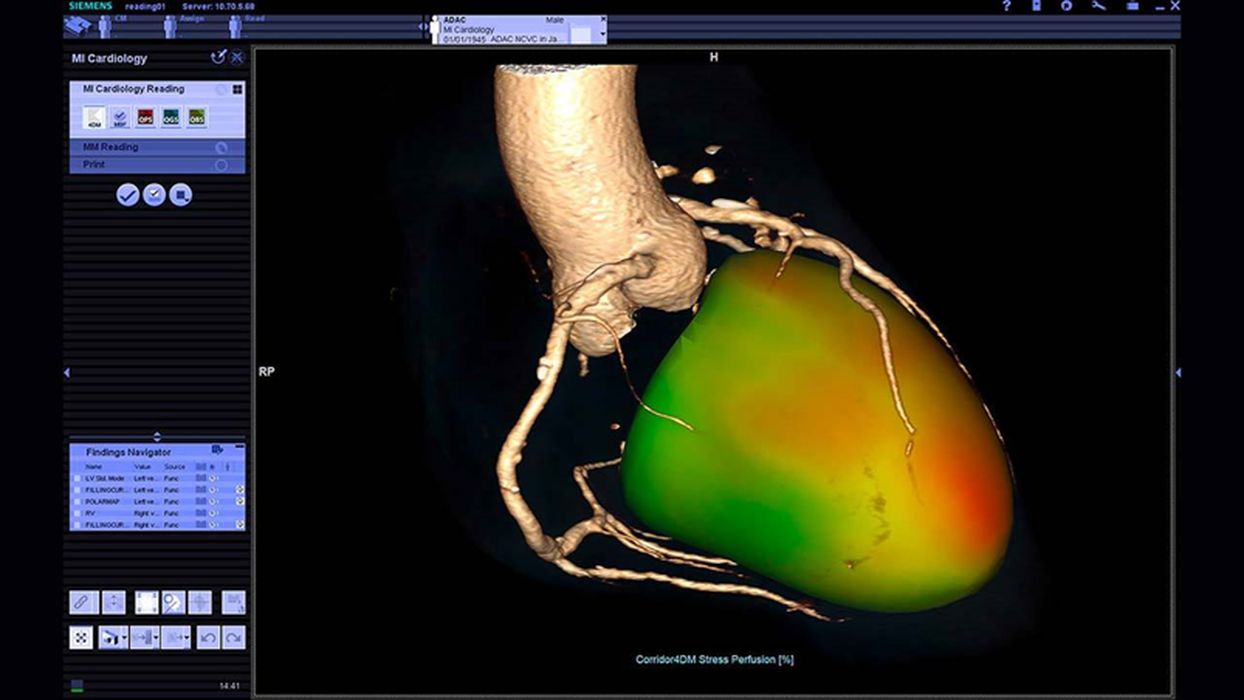

Siemens Healthineers

We have covered how Siemens Healthineers is changing the way med-tech is utilizing 3D printing today. With its US$16.4B acquisition of Varian Medical Technologies, the resources for integrating 3D printing into its innovative, life-saving products has substantially increased.

Just last year, Siemens Healthineers and Materialise partnered to bring 3D printing capabilities to hospitals around the globe. Specifically, Mimics inPrint, a software necessary to make anatomical models using patient specifications, will allow radiologists to turn a patient’s body scan data into a digital 3D printable model. The software will be available as an app that will provide physicians an added dimension to medical imaging and help save lives.